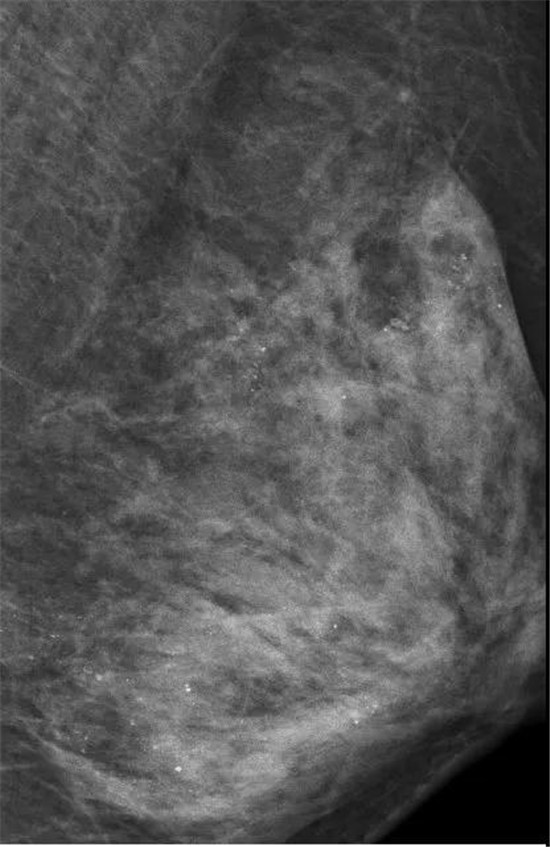

乳房没了,但这场大抢救却依旧在进行。医生在对她的左侧乳房进行乳腺X线检查时,发现里面全部都是细小如沙子一样的钙化灶,布满整个乳腺。

在X光片下,朱女士的乳腺里

满是星星点点的钙化灶